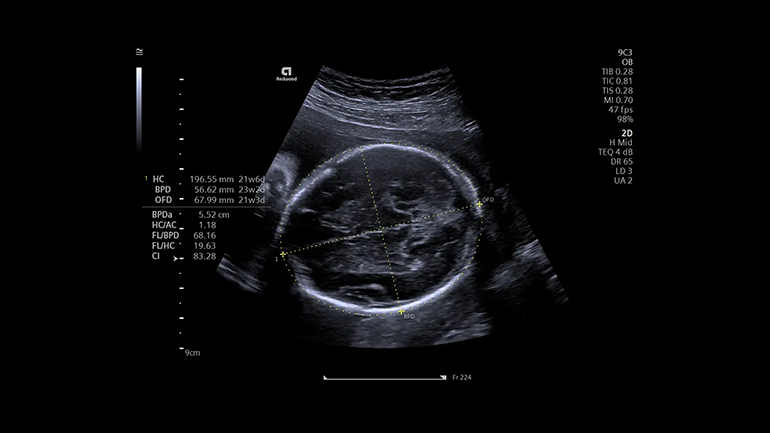

Технология автоматизации процесса измерений в 2D-, M- и допплеровских режимах eSie Measure. Технология eSie Measure позволяет выполнять количественные измерения одним нажатием кнопки, тем самым сокращается количество ручных действий врача-диагноста и повышается воспроизводимость результатов. Технология автоматических перинатальных измерений eSie OB. eSie OB автоматизирует выполнение биометрических измерений при акушерских исследованиях. Она не только уменьшает время сканирования и сокращает количество нажатий клавиш, но и повышает воспроизводимость УЗ- исследований.

Технология автоматических перинатальных измерений eSie OB. eSie OB автоматизирует выполнение биометрических измерений при акушерских исследованиях. Она не только уменьшает время сканирования и сокращает количество нажатий клавиш, но и повышает воспроизводимость УЗ- исследований. Технология автоматического исследования левых отделов сердца eSie Left Heart. Технология eSie Left Heart идентифицирует и автоматически очерчивает левый желудочек и левое предсердие, благодаря чему повышаются согласованность и воспроизводимость количественного анализа этих отделов сердца.